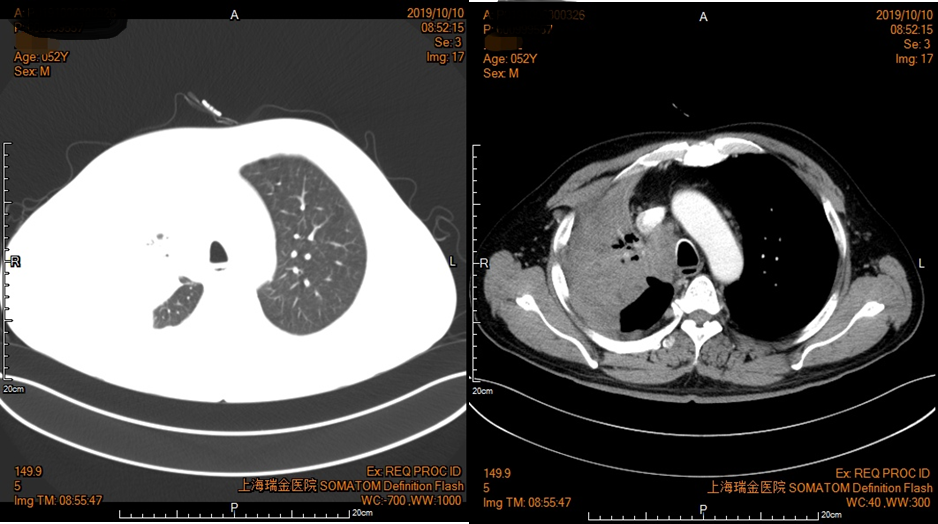

2019年10月10日胸部增强CT(图5):右肺门及上叶Ca伴右肺上叶阻塞性肺不张治疗后较前片(7月26日)范围减小,纵隔淋巴结肿大,左肺上叶肺气肿伴肺大疱。

图5 患者胸部CT影像资料(2019年10月10日)

2019年12月3日胸部增强CT(图6):右肺门及上叶Ca伴右肺上叶阻塞性肺不张治疗后较前片(10月10日)范围减小,纵隔淋巴结肿大,左肺上叶肺气肿伴肺大疱。

图6 患者胸部CT影像资料(2019年12月3日)